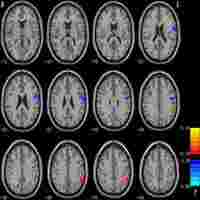

| Abstract | Altered resting-state functional connectivity has been found in patients with post-traumatic stress disorder (PTSD). However, the alteration of resting-state functional connectivity at whole-brain level in typhoon-traumatized individuals with PTSD remains largely unknown.Objectives:To investigate changes in whole-brain resting-state functional connectivity and brain network topology in typhoon-traumatized subjects with and without PTSD.Design:Cross-sectional study.Methods:Twenty-seven patients with typhoon-related PTSD, 33 trauma-exposed controls (TEC), and 30 healthy controls (HC) underwent resting-state functional MRI scanning. The whole brain resting-state functional connectivity network was constructed based on the automated anatomical labeling atlas. The graph theory method was used to analyze the topological properties of the large-scale resting-state functional connectivity network. Whole-brain resting-state functional connectivity and the topological network property were compared by analyzing the variance.Results:There was no significant difference in the area under the curve of γ, λ, σ, global efficiency, and local efficiency among the three groups. The PTSD group showed increased dorsal cingulate cortex (dACC) resting-state functional connectivity with the postcentral gyrus (PoCG) and paracentral lobe and increased nodal betweenness centrality in the precuneus relative to both control groups. Compared with the PTSD and HC groups, the TEC group showed increased resting-state functional connectivity between the hippocampus and PoCG and increased connectivity strength in the putamen. In addition, compared with the HC group, both the PTSD and TEC groups showed increased connectivity strength and nodal efficiency in the insula.Conclusion:Aberrant resting-state functional connectivity and topology were found in all trauma-exposed individuals. These findings broaden our knowledge of the neuropathological mechanisms of PTSD. |